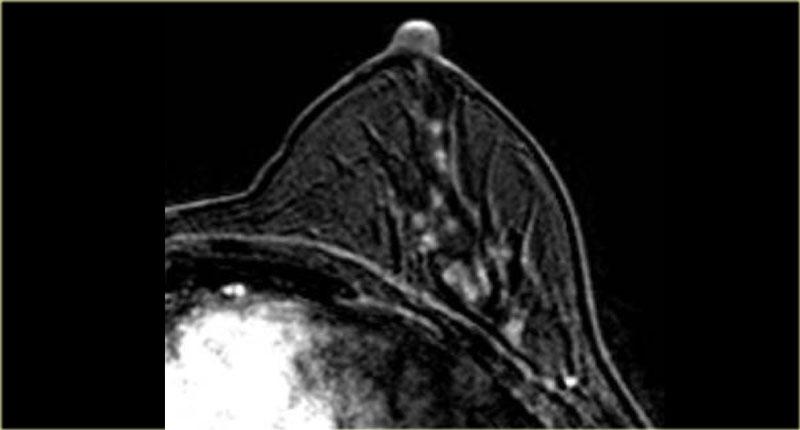

Hình ảnh ngoài cùng bên trái cho thấy một khối bất thường có lan rộng theo ống tuyến, và

bên phải là một khối bất thường lan đến thành ngực nhưng không xâm lấn vào thành ngực.

Không có ngấm thuốc ở thành ngực.